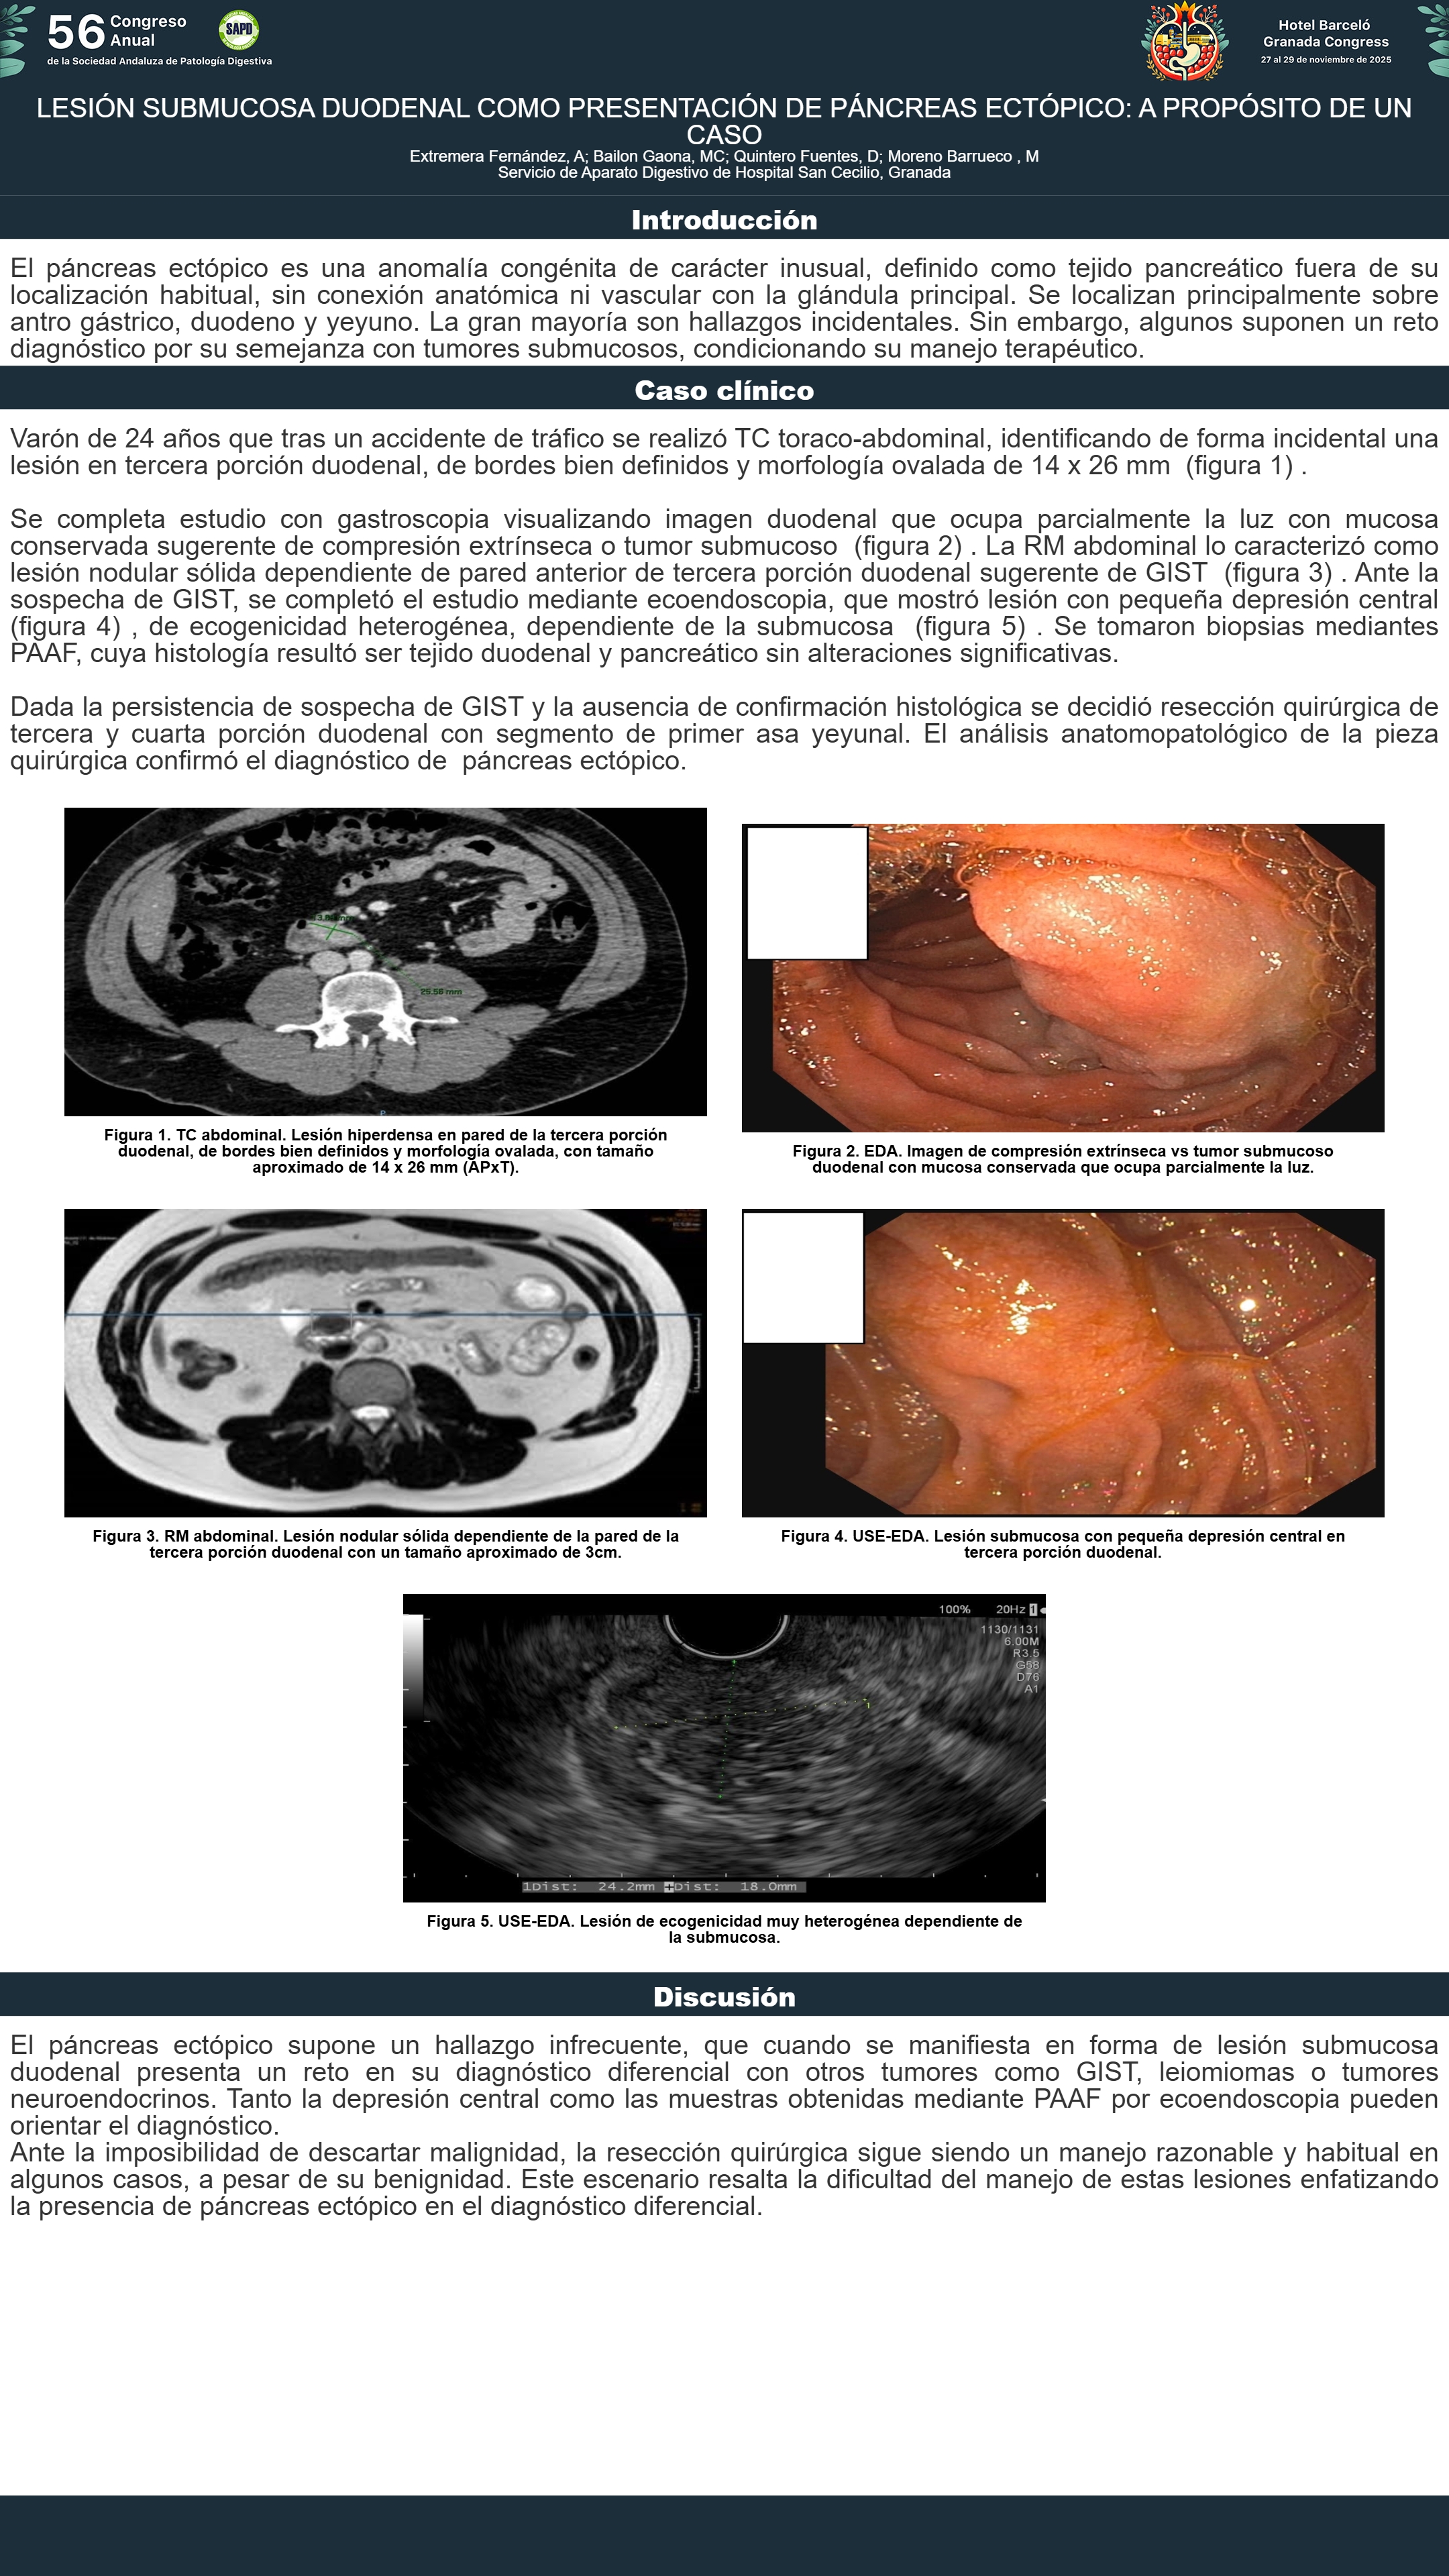

[CP-137] LESIÓN SUBMUCOSA DUODENAL COMO PRESENTACIÓN DE PÁNCREAS ECTÓPICO: A PROPÓSITO DE UN CASO